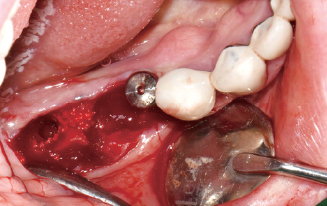

Wifi-Mesh 준비 및 다듬기

#45 & #46 골 결손 부위에

Wifi-Mesh 위치시킴

#46 발치와 부위에 시행한

Open membrane technique